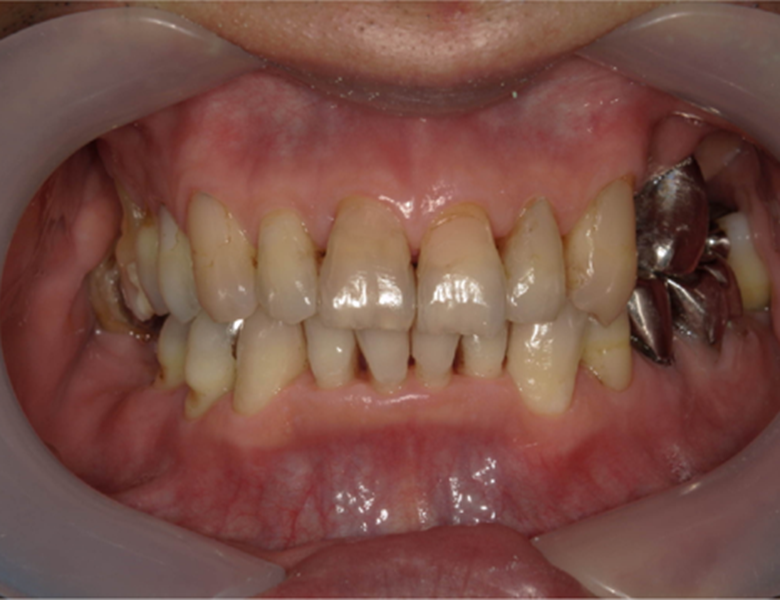

治療後

武蔵中原の歯医者、中林デンタルケアークリニックの予防症例、治療後

術後の経過・現在の様子 プラークや歯石の除去により歯ぐきが健康で引き締まった状態になり、腫れや出血も見られなくなりました。

お口全体の環境が整ったため、中断されていた虫歯治療を再開することができました。

今後も定期的にクリーニングを実施し、歯周病を予防していく予定です。